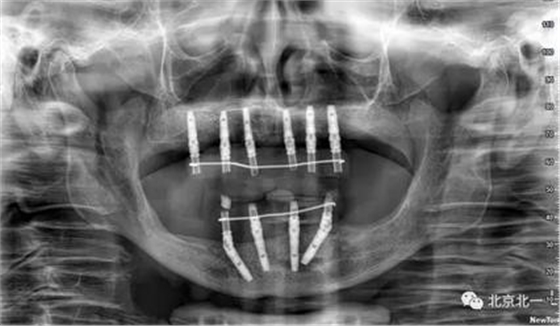

術(shù)中情況。

術(shù)后CBCT檢查,位置方向理想位置。